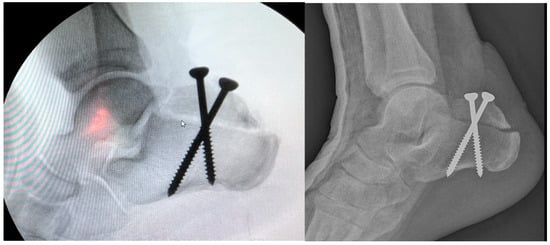

After debridement of the necrotic area, the soft tissue defect was about 6 cm × 7 cm. Figure 9. The fracture was reduced and fixed through the ORIF method with two canulated screws. Figure 10.

Figure 10. X-ray view after ORIF.